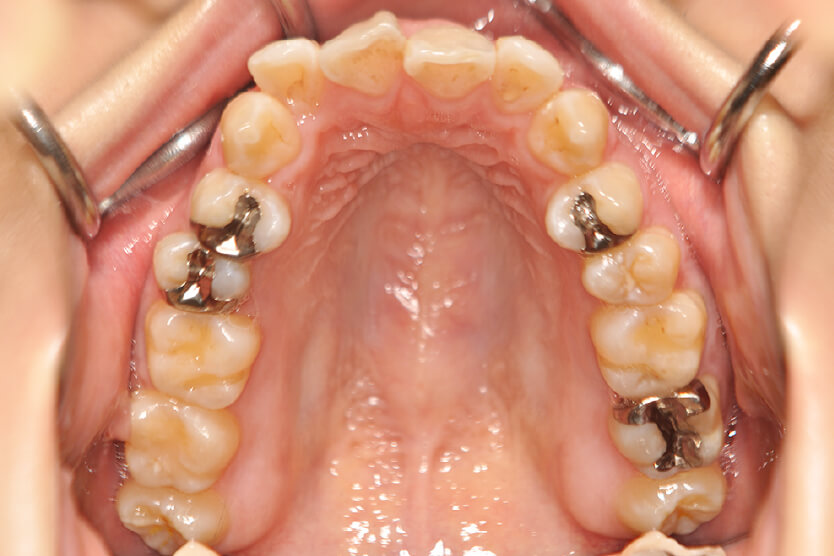

動的治療終了時

症例 症例 症例 症例

治療内容の詳細 初診時21歳の女性で、出っ歯、下顎前歯部のがたつきを気にされ来院されました。

検査の結果、上顎前突、上下顎前歯部叢生および開咬を伴うアングルⅡ級1類不正咬合と診断しました。

治療としては、上下左右第一小臼歯を抜歯して、セルフライゲーションブラケット装置(デーモンシステム)とマウスピース型矯正装置(インビザライン)で配列を行いました。

この際、上顎に歯科矯正用アンカースクリューを設置し上顎前歯部後退時の土台としました。

開咬については、顎間ゴムの協力もあり改善されました。